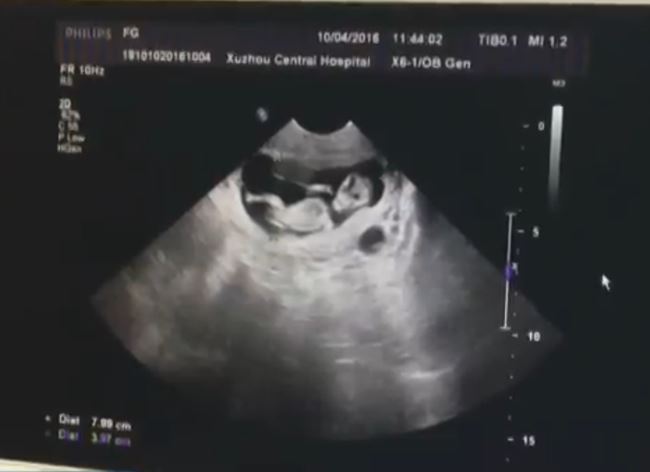

進入診間後,醫師更覺得不可置信,女孩的發育都還不完全,就像是未成年的身體,怎麼可能會有20歲,經檢查後,確定女孩已經懷孕12周,看診的過程,這名女孩從頭到尾都沒有出聲,兩名中年人就像代言人般,所有的問題都他們代為由女童回答。

▼醫生確認女孩已經懷孕12周。(圖/荔枝網)